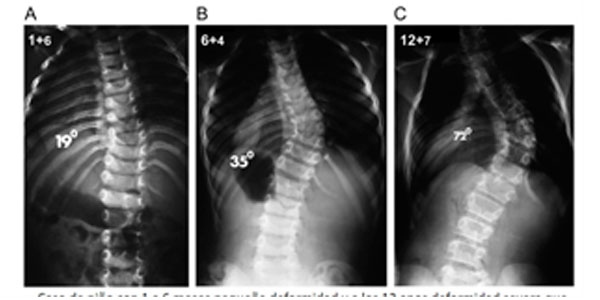

Se necesitará controles periódicos (4-6 meses) para comparar con estudios radiográficos si la curva está aumentando o está detenida.

El 75 % tienden a progresar, con frecuencia la cirugía precoz permite que el paciente evite una cirugía mucho más extensa más adelante.

Paciente de 1 año y 8 meses con escoliosis congénita progresiva, se realizó resección de hemivertebra con colocación de tornillos transpediculares

La columna vertebral crece rápidamente en los primeros 5 años de vida y en la adolescencia, es importante que en estos periodos tener una observación estricta por el especialista en escoliosis